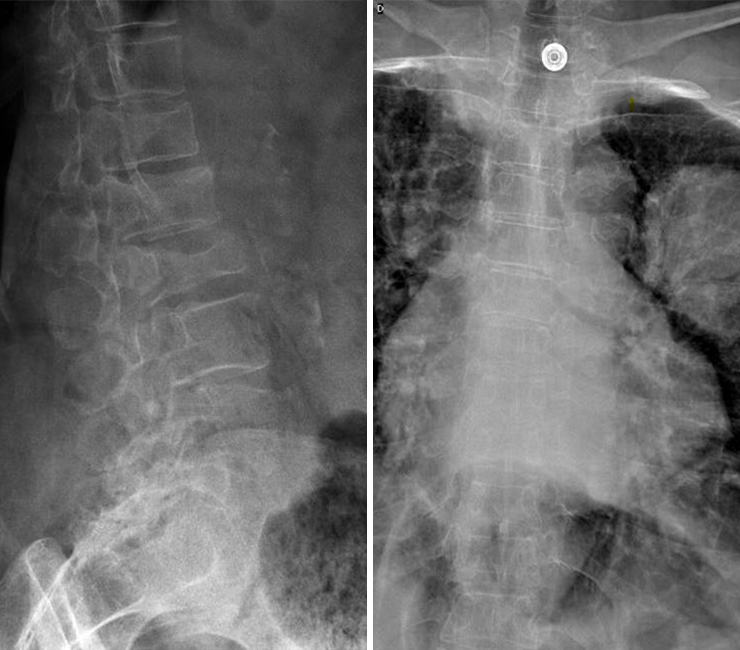

Vous faites réaliser une radiographie du rachis dorso-lombaire dont voici les clichés. Figure 1 (Salomé Abdellaoui, La Revue du Praticien)

Question 4 - Qu’identifiez-vous sur cette radiographie (une ou plusieurs réponses exactes) ?

Il existe bien une image pulmonaire suspecte mais elle est située dans le poumon gauche (légendée par une étoile).

Il s’agit d’une électrode d’électrocardiogramme.

On observe sur les radiographies une fracture vertébrale de L2, qui n'a pas de caractère évident de malignité (voir la suite du dossier), ainsi que des fractures plateaux supérieurs des vertèbres T12 et L1. Figure 2 (Salomé Abdellaoui, La Revue du Praticien)